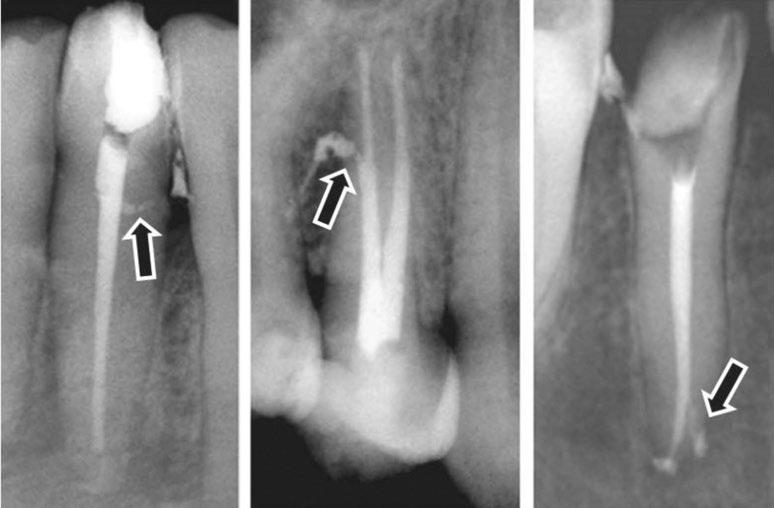

Clinical case performed by Dr. Benedict Bachstein (Figures 1-3)

The patient was diagnosed with irreversible pulpitis in tooth number 14, which presented multiple canals with highly complex anatomies. All canals were instrumented to 25/.04 and cleaned with Odne®Clean following the recommended clinical protocol. The use of Odne®Clean enabled the identification of five canal orifices and clearing of apical deltas.

Clinical case performed by Dr. Brett Gilbert (Figures 4 and 5)

In this case, Dr. Gilbert was initially unable to locate the MB2 canal, despite thorough attempts using ultrasonic and a microscope. After performing the irrigation protocol with Odne®Clean, the MB2 became visible. Following activation, the filling material extended completely through the MB2.

Clinical case performed by Dr. Sameer Jain (Figures 6 and 7)

The RCT involved a deep split tri-furcated premolar. Use of Odne®Clean enabled access to the advanced canal anatomy.